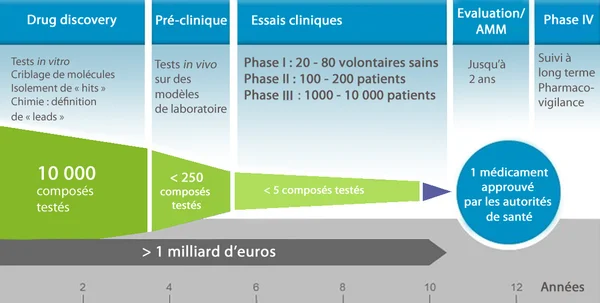

Le passage à l'essai humain représente le Rubicon de toute recherche médicale. Pour le médicament de repousse dentaire, ce protocole est conçu avec une prudence militaire, la sécurité étant le maître-mot absolu à ce stade précoce. L'étude clinique de Phase I a débuté récemment, avec des fenêtres temporelles situées entre juillet et septembre 2024 selon les sources. Ce décalage s'explique par les procédures administratives et logistiques inhérentes aux essais médicaux. L'objectif de cette phase n'est pas encore de prouver l'efficacité esthétique, mais de confirmer que le médicament ne présente pas de toxicité dangereuse pour l'organisme humain.

Le design de cet essai est extrêmement encadré pour maximiser la pertinence des données recueillies tout en minimisant les risques pour les participants. Les données cliniques réelles restent confidentielles pour le moment, protégées par le secret industriel et médical en attendant les premières publications ou communications officielles. Cette confidentialité est habituelle dans les essais précoces, évitant toute spéculation prématurée qui pourrait influencer les résultats ou créer de faux espoirs chez le public. Cependant, la structure même de cet essai nous renseigne sur la stratégie des chercheurs pour les années à venir.

Comment se déroule la Phase I à l'hôpital Kitano ?

Le protocole actuel se déroule principalement à l'hôpital Kitano d'Osaka, le fief du Dr Takahashi. Il implique un groupe restreint de 30 hommes âgés de 30 à 64 ans. Le choix de ne sélectionner que des hommes pour cette première phase vise à éliminer les variables hormonales féminines qui pourraient complexifier l'analyse des effets secondaires. Un critère de sélection crucial est que chaque participant doit manquer d'au moins une dent postérieure. Cette exigence permet de disposer d'un site de mesure clair pour observer une éventuelle repousse, sans attendre des années qu'une dent tombe naturellement.

La durée de l'essai est fixée à onze mois, une période jugée suffisante pour observer la tolérance immédiate et les premiers signes d'activité biologique. Les chercheurs surveilleront de près la réponse de l'organisme à l'administration intraveineuse de TRG035, en analysant le sang et les tissus gingivaux. Si cette première phase confirme l'innocuité du produit, elle ouvrira la porte à des phases plus vastes. La prudence est de mise : même si les résultats sur le furet étaient excellents, le corps humain peut réagir de manière imprévisible, ce qui justifie cette approche progressive par paliers de sécurité.

Qui seront les prochains patients après les adultes ?

Si la Phase I chez l'adulte est concluante, la stratégie de Toregem BioPharma prévoit une transition rapide vers une population pédiatrique. La prochaine étape ciblera les enfants âgés de 2 à 7 ans souffrant d'anodontie congénitale, une condition rare et dévastatrice où les enfants naissent avec peu ou pas de dents du tout. Pour ces patients, l'enjeu est vital : sans dents, l'apprentissage de la mastication et le développement de la parole sont gravement compromis, ainsi que la structure de la mâchoire. Faire repousser des dents naturelles chez ces enfants serait une victoire médicale et humaine inestimable.

À plus long terme, l'ambition est d'élargir l'indication au grand public. L'objectif final est que le médicament puisse être administré à toute personne ayant perdu une dent, que ce soit à cause d'une carie, d'un traumatisme ou d'une maladie parodontale. Le Dr Takahashi envisage un futur où l'on pourrait simplement se faire une piqûre après une extraction pour voir la dent repousser naturellement. Selon le calendrier actuel, si les essais se déroulent sans accroc, la mise sur le marché commercial est visée pour l'année 2030. Cela nous laisse encore quelques années de patience avant de voir ce traitement arriver dans les cabinets français.